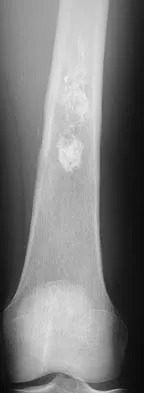

Examination of an obese 3-year-old girl reveals 30 degrees of unilateral genu varum. A radiograph of the involved leg with the patella forward is shown in Figure 10. Management should consist of

Explanation

The clinical scenario describes infantile tibia vara (Blount's disease). The radiograph shows severe deformity with the characteristic Langenskiold stage 3 changes of the medial proximal tibial metaphysis that distinguish it from physiologic bowing. The preferred treatment is proximal tibiofibular osteotomy with acute correction into slight valgus to unload the damaged area of the physis. This method provides the best results in patients younger than age 4 years. Continued observation would result in progressive deformity. Bracing is most effective in younger children with less severe deformity. Lateral proximal tibial hemiepiphysiodesis relies on growth of the injured medial physis for correction and would result in severe tibial shortening in this young child. Complete epiphysiodesis also produces severe shortening and requires multiple lengthening procedures. Johnston CE II: Infantile tibia vara. Clin Orthop 1990;255:13-23.